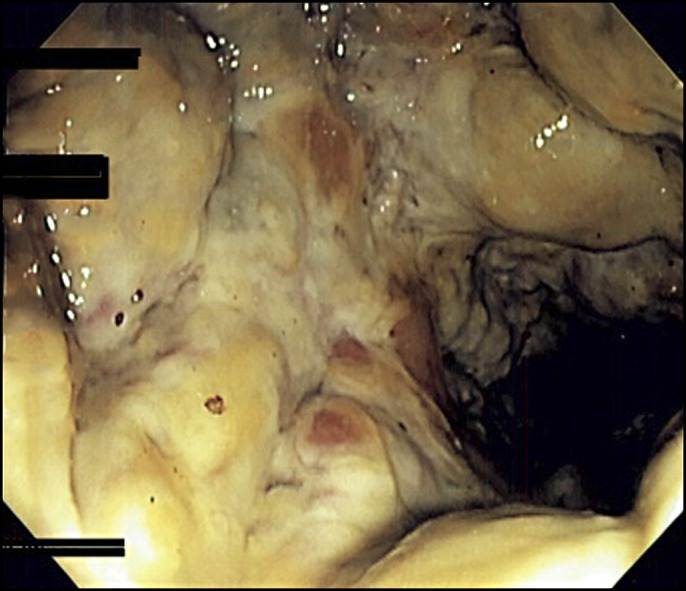

Tổn thương viêm mức độ nặng ở đại trực tràng sau thụt cà phê